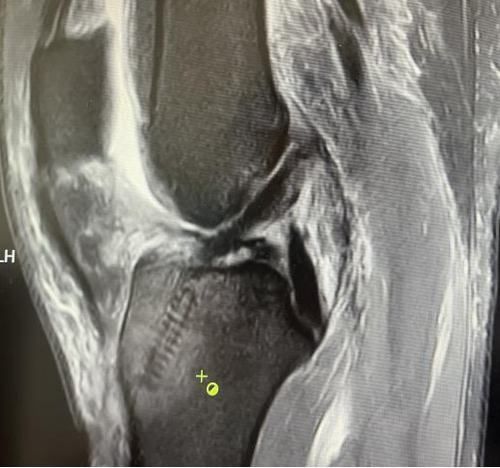

膝關節(jié)韌帶損傷磁共振

我院骨科三病區(qū)近期收治了4名膝關節(jié)交叉韌帶損傷患者。25歲的齊先生,因打籃球時不慎扭傷左膝,致右膝腫痛,遂來我院治療;30歲趙先生酷愛足球,扭傷右膝關節(jié)來我院就診;50歲的張先生、42歲劉先生因騎車滑倒摔傷、膝關節(jié)腫痛不適、活動受限,收治入院。骨科三病區(qū)李鵬主任團隊詳細查體以及完善影像學檢查后進行診斷:幾位患者共同診斷均有“前交叉韌帶損傷”,不同程度合并有“半月板損傷”、“股骨軟骨損傷”、“內(nèi)側副韌帶斷裂”。

在與患者溝通時,李鵬主任表示:“鑒于年輕患者后期對運動要求高,恢復前交叉韌帶解剖和生理功能極其重要,同時考慮早期功能的鍛煉和美觀程度,建議行關節(jié)鏡微創(chuàng)手術。該手術沒有傳統(tǒng)“開刀”的恐懼不安,有的只是術后的快速康復和手術部位幾處微不可見的小疤痕?!?